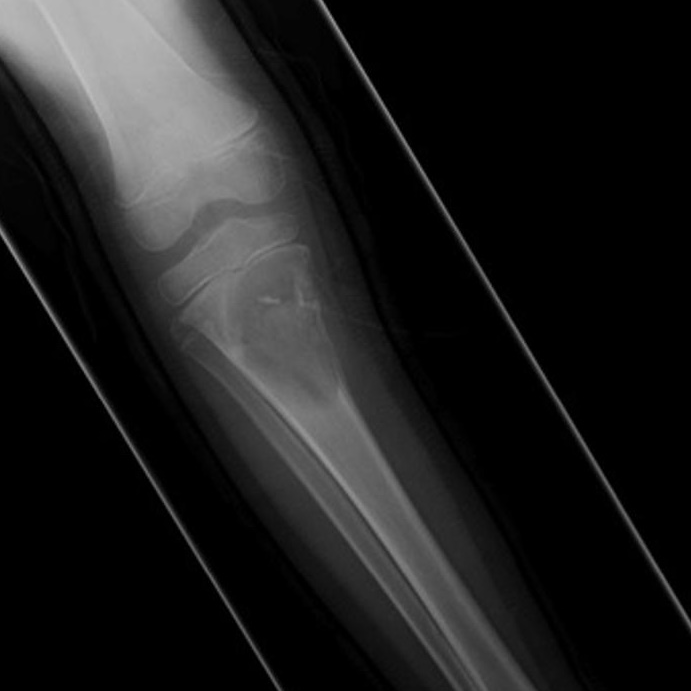

Welche Differentialdiagnose ist auf Grundlage des vorliegenden Röntgenbildes, der MRT-Befunde und der klinischen Informationen am wahrscheinlichsten? Anamnese: Schmerzhaftes Knie bei einem 6-jährigen Jungen.